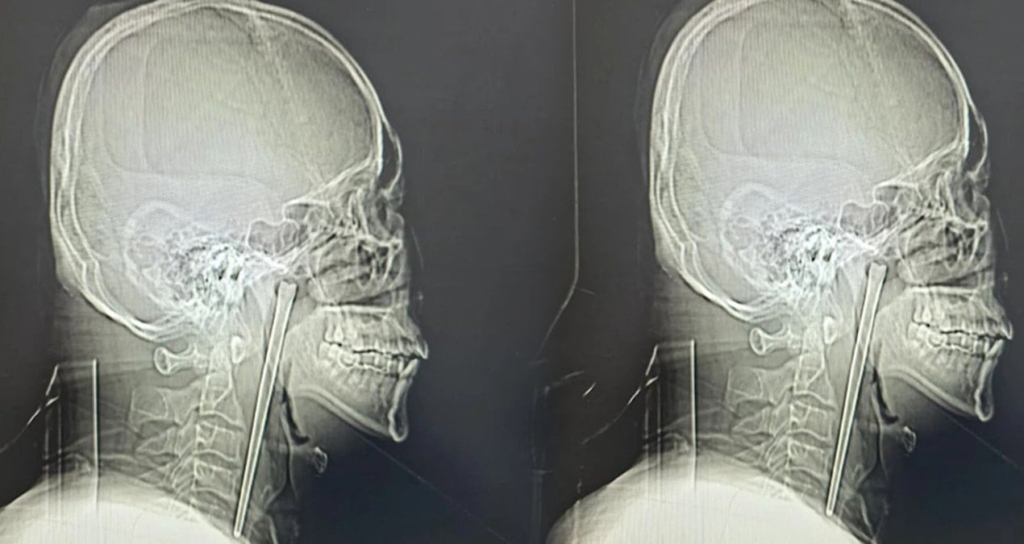

Dalian Belediye Merkez Hastanesi’ne boğazında şiddetli ağrı ve yabancı cisim hissi şikayetiyle giden Bay Wang’ın yapılan röntgen muayenesinde, boğaz bölgesine saplanmış metal bir mil tespit edildi. Hastanın, doktorların sorusu üzerine durumu onaylayarak sekiz yıl önce yemek yerken yanlışlıkla bir metal yemek çubuğu yuttuğunu ifade ettiği bildirildi.

TEK PARÇA HALİNDE ÇIKARILDI